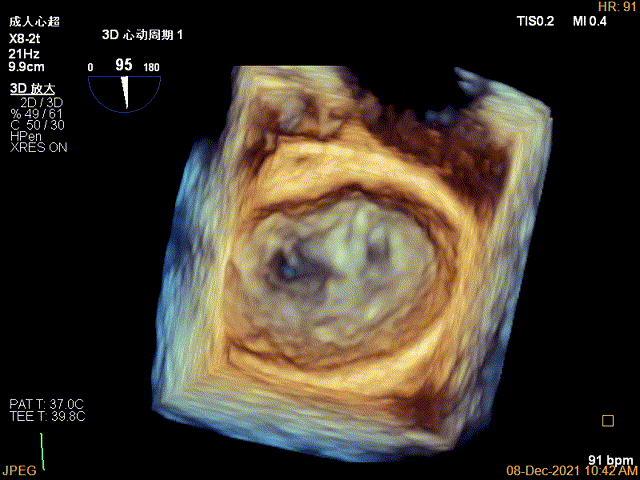

3D视图下调整夹子位置及Rotate

X-plane:下夹子尝试先捕获2区瓣叶

夹子关闭过程中,Color提示2区反流逐渐减少,残余反流位于夹子外侧

3D-VIEW验证结果

3D-Color-view验证残余分流位于外侧